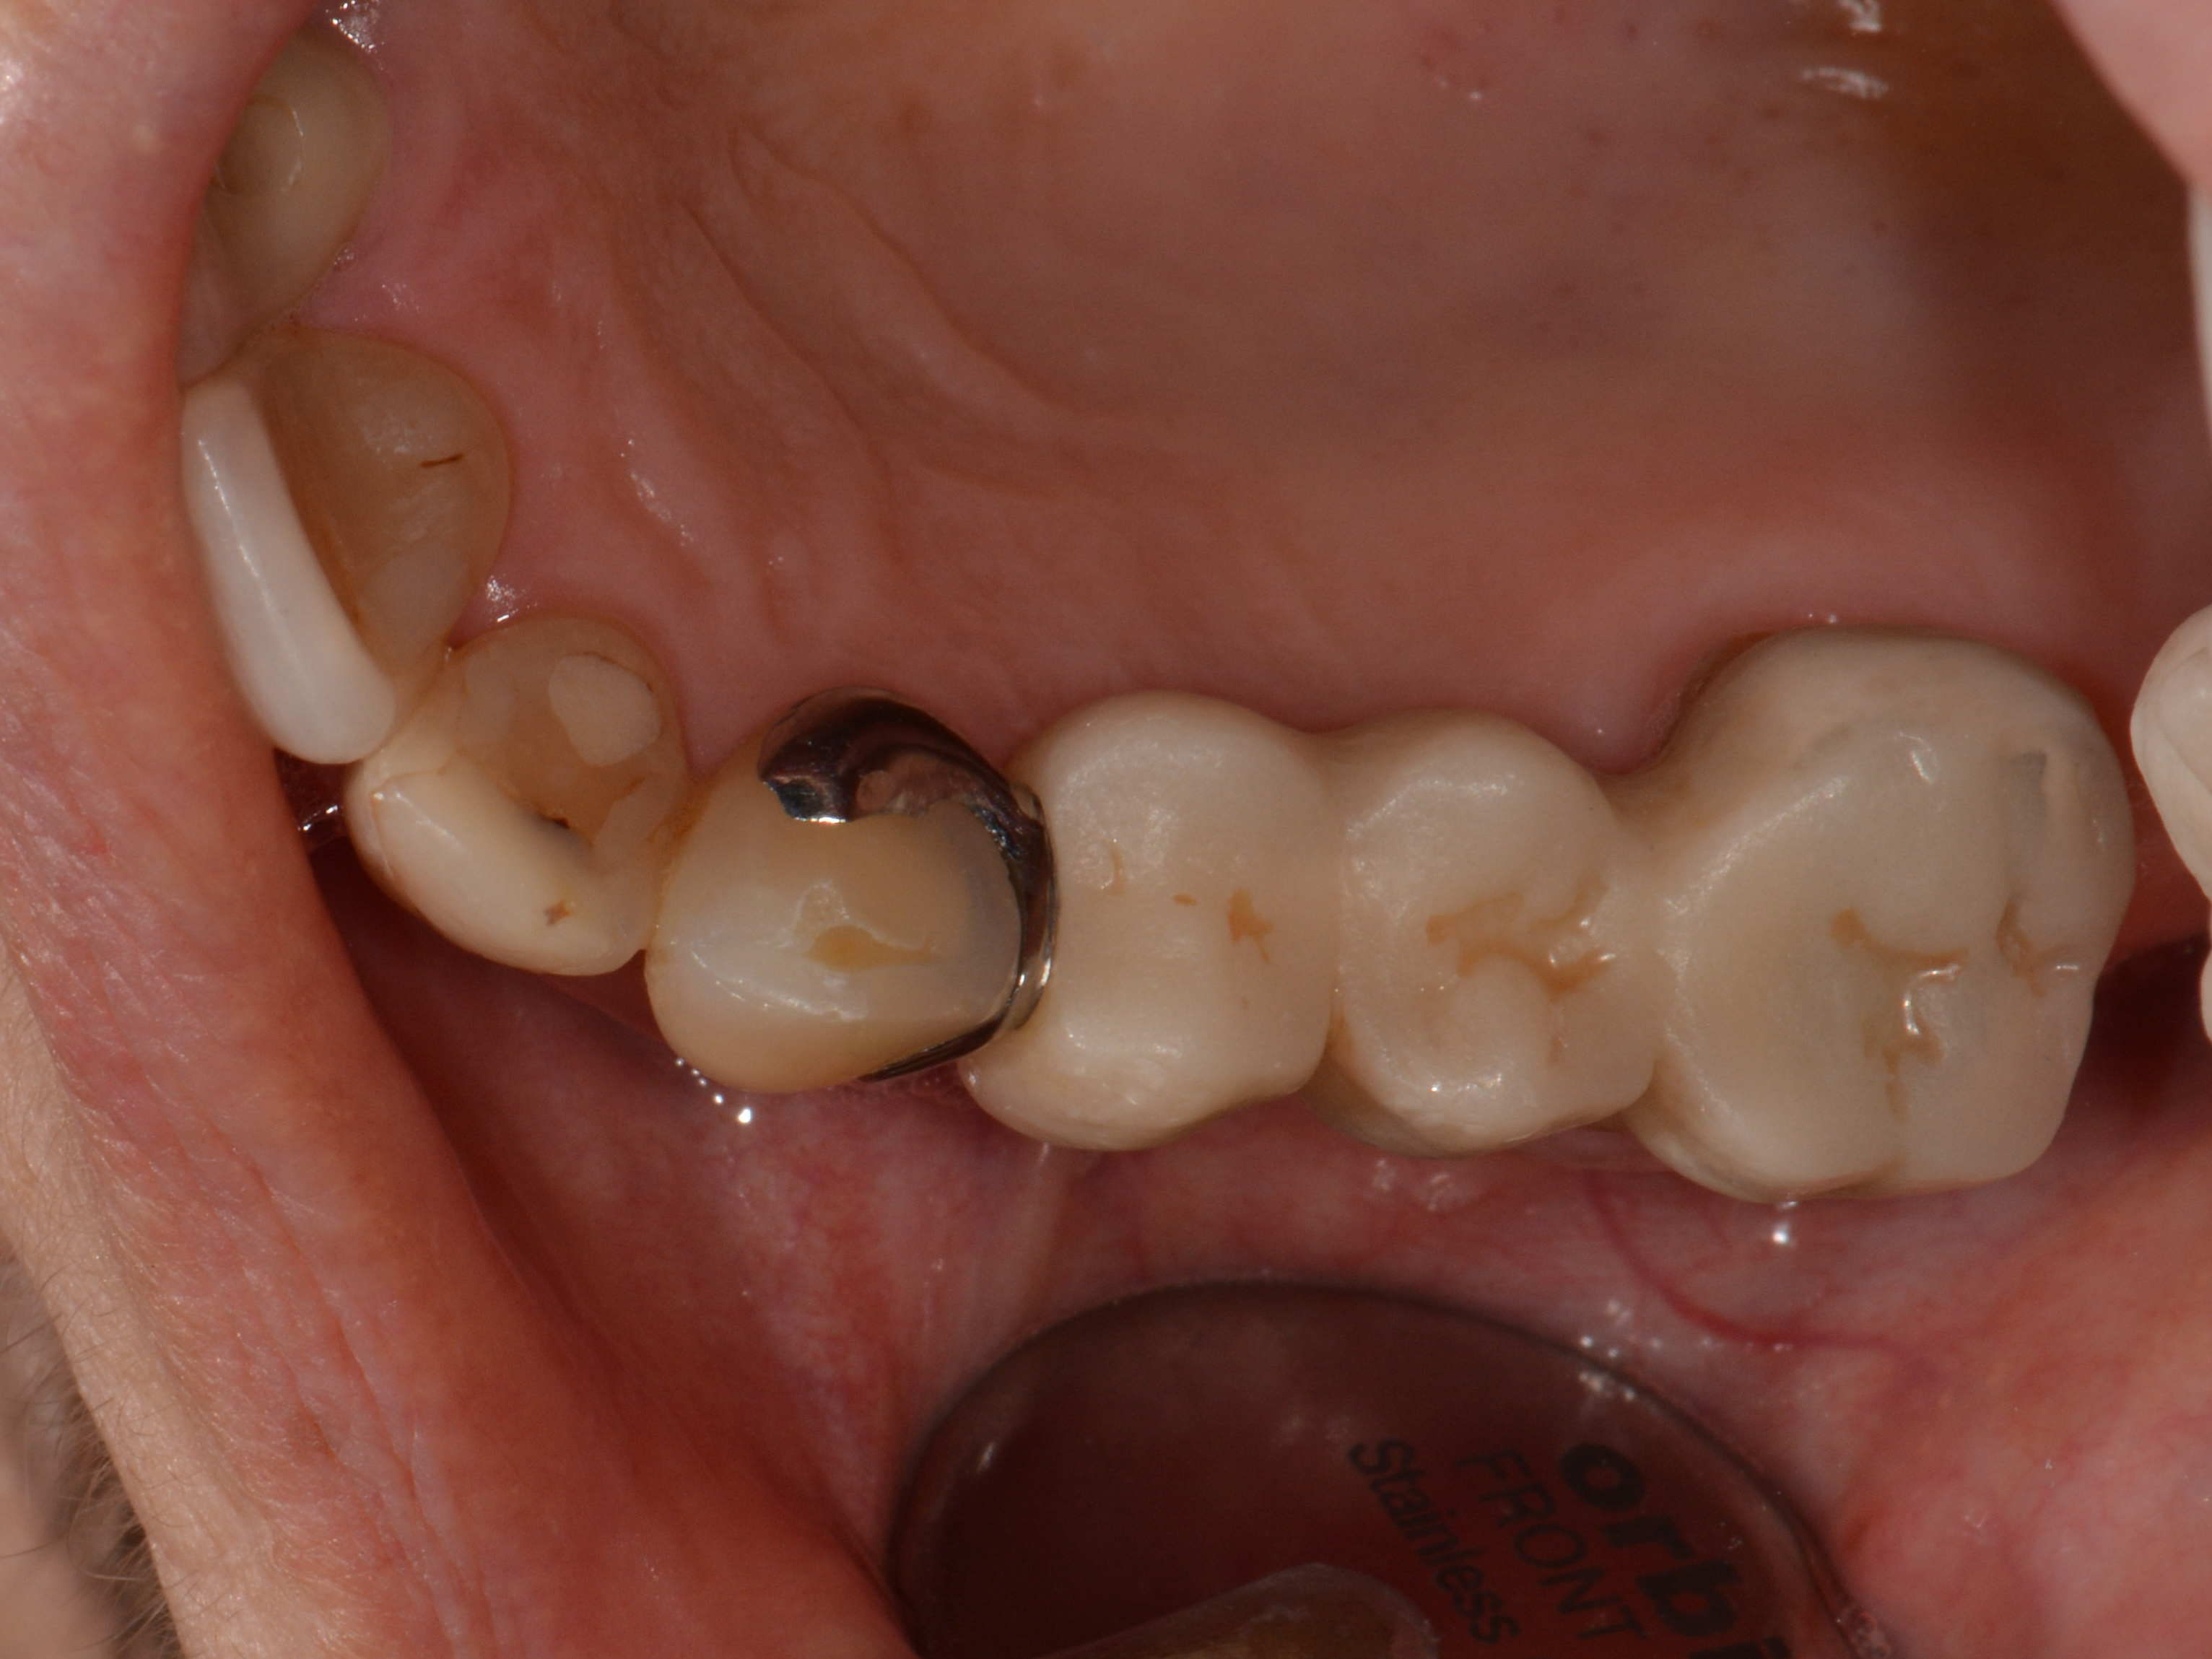

Fig. 1: Before treatment. Provisional bridge from tooth #13 to tooth #16.

A 56-year-old female patient presented to our outpatient department with a Kennedy Class II, missing teeth #14 and 15, and requested closure of the gap. Her existing restoration was a provisional bridge from tooth #13 to tooth #16 (Fig. 1). The patient’s general medical history did not reveal any abnormalities. The patient was informed of the available treatment options, taking her general medical and dental history into consideration. In light of the patient’s request for a fixed denture, the options were a bridge from tooth #13 to tooth #16 or implants in regions #14 and 15 with subsequent crown restoration of the implants and tooth #16. Based on the integrity of tooth #13, the patient opted for an implant restoration. This was followed by comprehensive briefing on the clinical procedure and the taking of a CBCT scan and an impression of the situation.

The provisional bridge was modified at the base to create space in case of swelling and inserted with methacrylate-based temporary luting material (Bifix Temp, VOCO). The screw-retained final restorations were fabricated from a multilayered monolithic zirconia (DD cubeX2 ML, Dental Direkt; Fig. 14).

Fig. 14: Screw-retained final restorations.